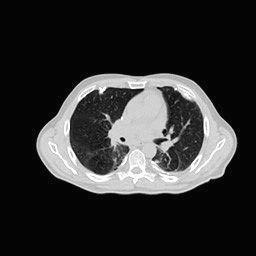

4.3 Few-View CT Reconstruction

In this section, the reconstruction performance of our proposed framework under few-view conditions will be tested. For the parallel-beam and fan-beam geometry, the number of views increases from to , uniformly distributing from to and to respectively. Such settings provide a complete benchmark of reconstruction performance, ranging from extremely sparse to relatively complete, full-view CT reconstruction. The experiment results are shown in Fig.5. Additionally, the ground truth, few-view ( views), and full-view ( views) CT reconstruction results of different methods are shown in the first and third rows of Fig.7 (parallel-beam, LIDC-IDRI dataset), and Fig.8 (fan-beam, LIDC-IDRI dataset).

(a) Ground Truth

43.87dB

(b) ASD-POCS

47.96dB

(c) RBP-DIP

34.46dB

(d) DIP

26.63dB

(e) MED50

29.03dB

(f) RED-CNN

16.31dB